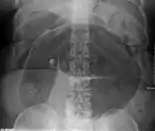

An x-ray of a person with a small bowel volvulus.

Plain X ray of a cecal volvulus